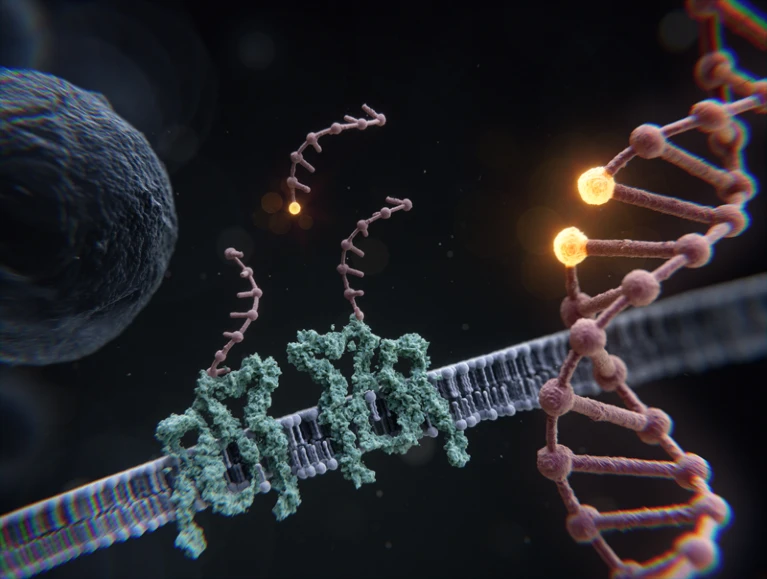

三、大片段DNA插入

2023 年底,美国和英国监管机构批准了首个基于 CRISPR 的基因编辑疗法,用于治疗镰状细胞病和输血依赖性地中海贫血β——这是基因组编辑作为临床工具的重大胜利。

CRISPR 及其衍生物使用短可编程 RNA 将 DNA 切割酶(如 Cas9)引导至特定的基因组位点。它们在实验室中通常用于禁用有缺陷的基因并引入小的序列变化。精确和可编程地插入跨越数千个核苷酸的较大DNA序列是很困难的,但新兴的解决方案可以让科学家替换有缺陷基因的关键片段或插入功能齐全的基因序列。加州斯坦福大学的分子遗传学家Le Cong和他的同事们正在探索单链退火蛋白(SSAP)——介导DNA重组的病毒衍生分子。当与禁用Cas9的DNA切片功能的CRISPR-Cas系统结合使用时,这些SSAP允许将多达2千碱基的DNA精确靶向插入人类基因组中。

其他方法利用一种称为素数编辑的基于CRISPR的方法引入短的“着陆垫”序列,这些序列选择性地募集酶,而酶又可以将大的DNA片段精确地拼接到基因组中。例如,2022 年,剑桥麻省理工学院的基因组工程师 Omar Abudayyeh 和 Jonathan Gootenberg 及其同事首次描述了通过位点特异性靶向元件 (PASTE) 进行可编程添加,这种方法可以精确插入多达 36 千碱基的 DNA[8]。Cong说,PASTE在培养的、患者来源的细胞的离体修饰方面特别有前景,并且潜在的初免编辑技术已经进入了临床研究的轨道。但对于人体细胞的体内修饰,SSAP可能提供更紧凑的解决方案:体积较大的PASTE机器需要三个独立的病毒载体进行递送,这可能会降低相对于双组分SSAP系统的编辑效率。也就是说,即使是相对低效的基因替代策略也足以减轻许多遗传疾病的影响。

这些方法不仅与人类健康有关。由北京中国科学院的Caixia Gao领导的研究人员开发了PrimeRoot,这是一种使用Prime Editing引入特定靶位点的方法,酶可以使用这些靶位点在水稻和玉米中插入多达20千个碱基的DNA[9]。Gao认为,该技术可用于赋予作物抗病性和抗病原体性,继续推动基于CRISPR的植物基因组工程的创新浪潮。“我相信这项技术可以应用于任何植物物种,”她说。